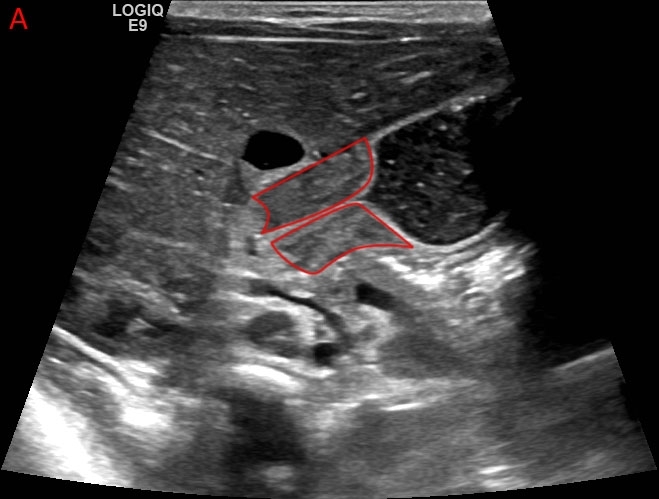

Pyloric Stenosis

When the diagnosis is suspected based on clinical presentation, the best next step in management is abdominal ultrasonography. The presence of a thick and elongated pylorus confirms the diagnosis.